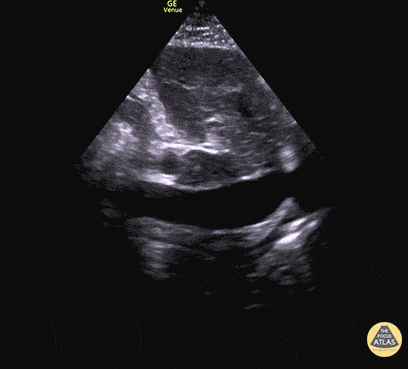

Sol ventrikül fonksiyonunun değerlendirilmesi

Sol ventrikül (LV) fonksiyonu dört pencerenin tamamında değerlendirilebilir; ancak genellikle parasternal uzun aks görüntüsünde en kolay şekilde incelenir. Değerlendirme iki şekilde yapılabilir:

Görsel (subjektif) tahmin

EPSS (End Point Septal Separation) ölçümü

Çok sayıda çalışma, acil hekimleri ile kardiyologlar arasında global kardiyak fonksiyonun görsel değerlendirilmesi açısından yeterli uyum olduğunu göstermiştir.

RUSH muayenesinde genellikle ejeksiyon fraksiyonunun tam yüzdesine odaklanmak yerine, sol ventrikül fonksiyonunu geniş kategoriler halinde sınıflandırırız:

Hiperkinetik (hiperdinamik)

Normal

Azalmış (düşük)

Azalmış sol ventrikül fonksiyonunu düşündüren hızlı ve pratik bulgular şunlardır:

Sol ventrikül kavite çapının sistolde yaklaşık üçte bir oranında küçülmemesi

Miyokardın sistol sırasında yeterince kalınlaşmaması

Mitral kapağın ön yaprağının diyastolde septuma yaklaşmaması

Buna karşılık hiperdinamik bir kalpte, sistolün zirvesinde ventrikül duvarlarının neredeyse tamamen kollabe olup birbirine temas ettiği izlenir.